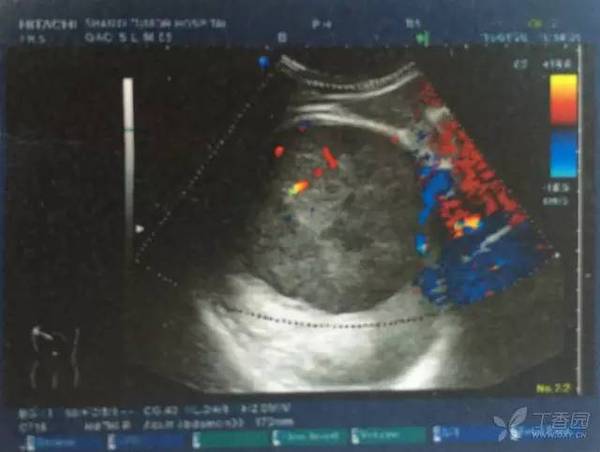

图 3 上消化道造影

上消化道造影结果示:贲门充盈缺损,建议胃镜检查,慢性胃炎。